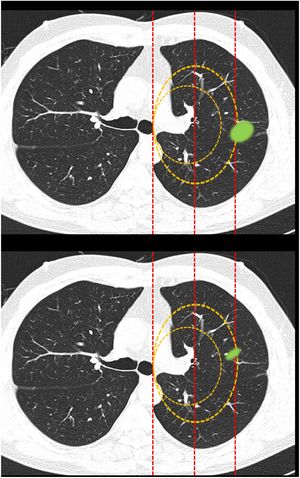

Classification of lesions extending beyond dividing lines (Fig. 2): this block evaluated the uniformity of criteria for classifying a lesion as central [according to a definition of centrality (in the inner two thirds) previously established in the text of the question] if it exceeded beyond dividing lines previously plotted on the image.

Fig. 2.This block evaluated the uniformity of criteria used to classify a lesion as central in lesions that extend beyond the dividing lines. Image 10: If a tumor located in the inner two thirds of the hemitorax is defined central, in your opinion, is the site of the nodule: central/peripheral? Image 11: If a tumor located in the inner two thirds of the hemitorax is defined as central, in your opinion, is the site of the nodule: central/peripheral?

Most survey respondents classified lesions based on whether most of their volume was on one side or the other of a dividing line previously traced on the image. Thus, lesions predominantly located on the peripheral side were classified as peripheral (image 10) (92.8%) and those predominantly located on the central side were classified as central (image 11) (79.2%), with no differences between specialties (Table 2).

Classification of lesions that extend beyond dividing lines (most of the volume in the peripheral zone versus most of the volume in the central zone). Most respondents believe that lesions should be classified according to where most of their volume is located. No significant differences were found between different specialty groups for either the first question or the second (aFisher exact test).